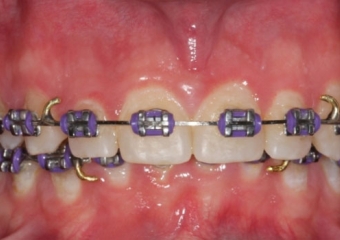

Sorriso inicial

Mordida inicial